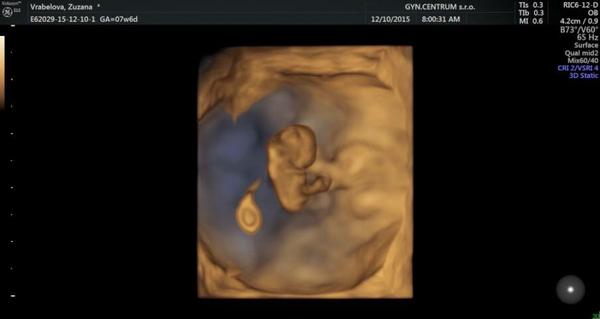

Ahojte baby, chcem Vám dodať troska pozitívnej energie.. Keď som zakladala tuto tému tajne som dúfala, aby nám to vyšlo všetkým. Po vyše roku sa zadarilo aj u nas.. Sme v 8tt a srdiečko bije ako zvon.. Mnohé baby z tejto témy už sa tiež vytešuju z malých bubliniek a Vám cakatelkam odporúčam bojujte a verte! Podarí sa to! 💕💞👣